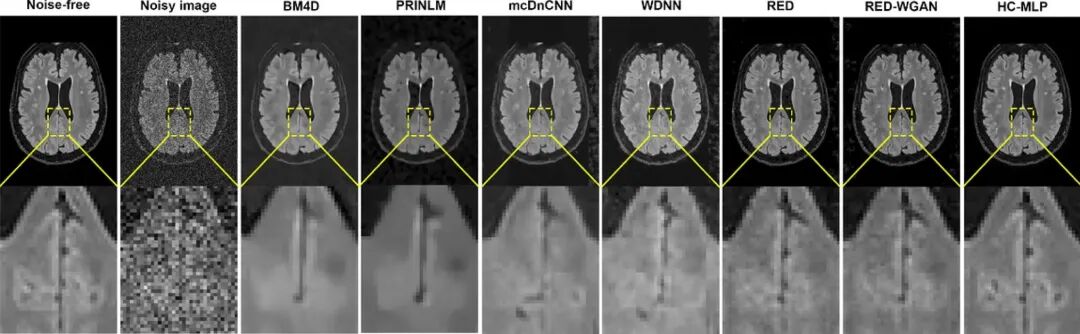

实验结果显示,该方法在3D-MRI 去噪中取得了显著优势,在客观数值指标上相比多种代表性传统方法与深度学习方法均有大幅提升,特别是在高噪声条件下仍能保持稳定表现(图2)。

图2 模型在MRI图像中的降噪效果